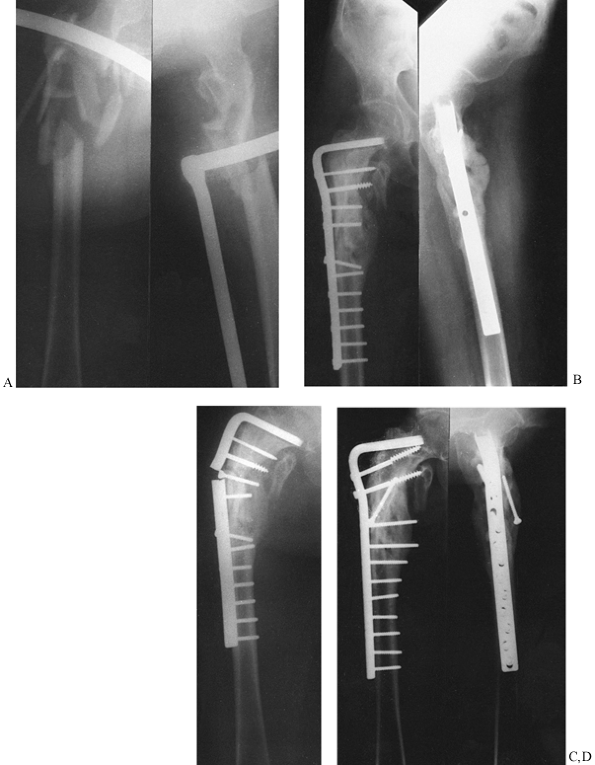

comminution, a large fragment of the posteromedial wall of the femur,

often including the lesser trochanter, splits free. This bony buttress

is important to the stability in the intertrochanteric region;

therefore, its comminution results in an unstable fracture.

stable or unstable. In the stable intertrochanteric fracture, the

posteromedial buttress remains intact or is minimally comminuted, and

therefore substantial collapse of the fracture fragments is unlikely.

In the unstable intertrochanteric fracture, however, a large segment of

the posteromedial wall is fractured free and comminuted, and therefore

the fracture tends to collapse into varus.

is useful because it further divides stable fractures into those

without comminution, those with minimal comminution, and those that are

subtrochanteric. A modification of Boyd’s classification is that of

Kyle, Gustilo, and Premer (81), which

recognizes four basic intertrochanteric fracture types. Type I

fractures consist of nondisplaced stable intertrochanteric fractures

without comminution (21%) (Fig. 19.19A). Type

II fractures represent stable, minimally comminuted but displaced

fractures (36%); these are fractures that, once reduced, allow a stable

construct (Fig. 19.19B). Stable fractures are

not a problem and hold up well with any type of fixation device. The

unstable type III intertrochanteric fracture (28%) is a problem

fracture and has a large posteromedial comminuted area (Fig. 19.19C). The unstable

type IV fracture is uncommon (15%) and consists of an intertrochanteric fracture with a subtrochanteric component (Fig. 19.19D).

This is the most difficult type of fracture to fix because of the great

forces imposed by muscle forces and weight bearing on the

subtrochanteric region of the femur (81,150).

![]() |

|

Figure 19.19. A: Type I intertrochanteric fracture. B: Type II intertrochanteric fracture. C: Type III intertrochanteric fracture. D: Type IV intertrochanteric fracture.